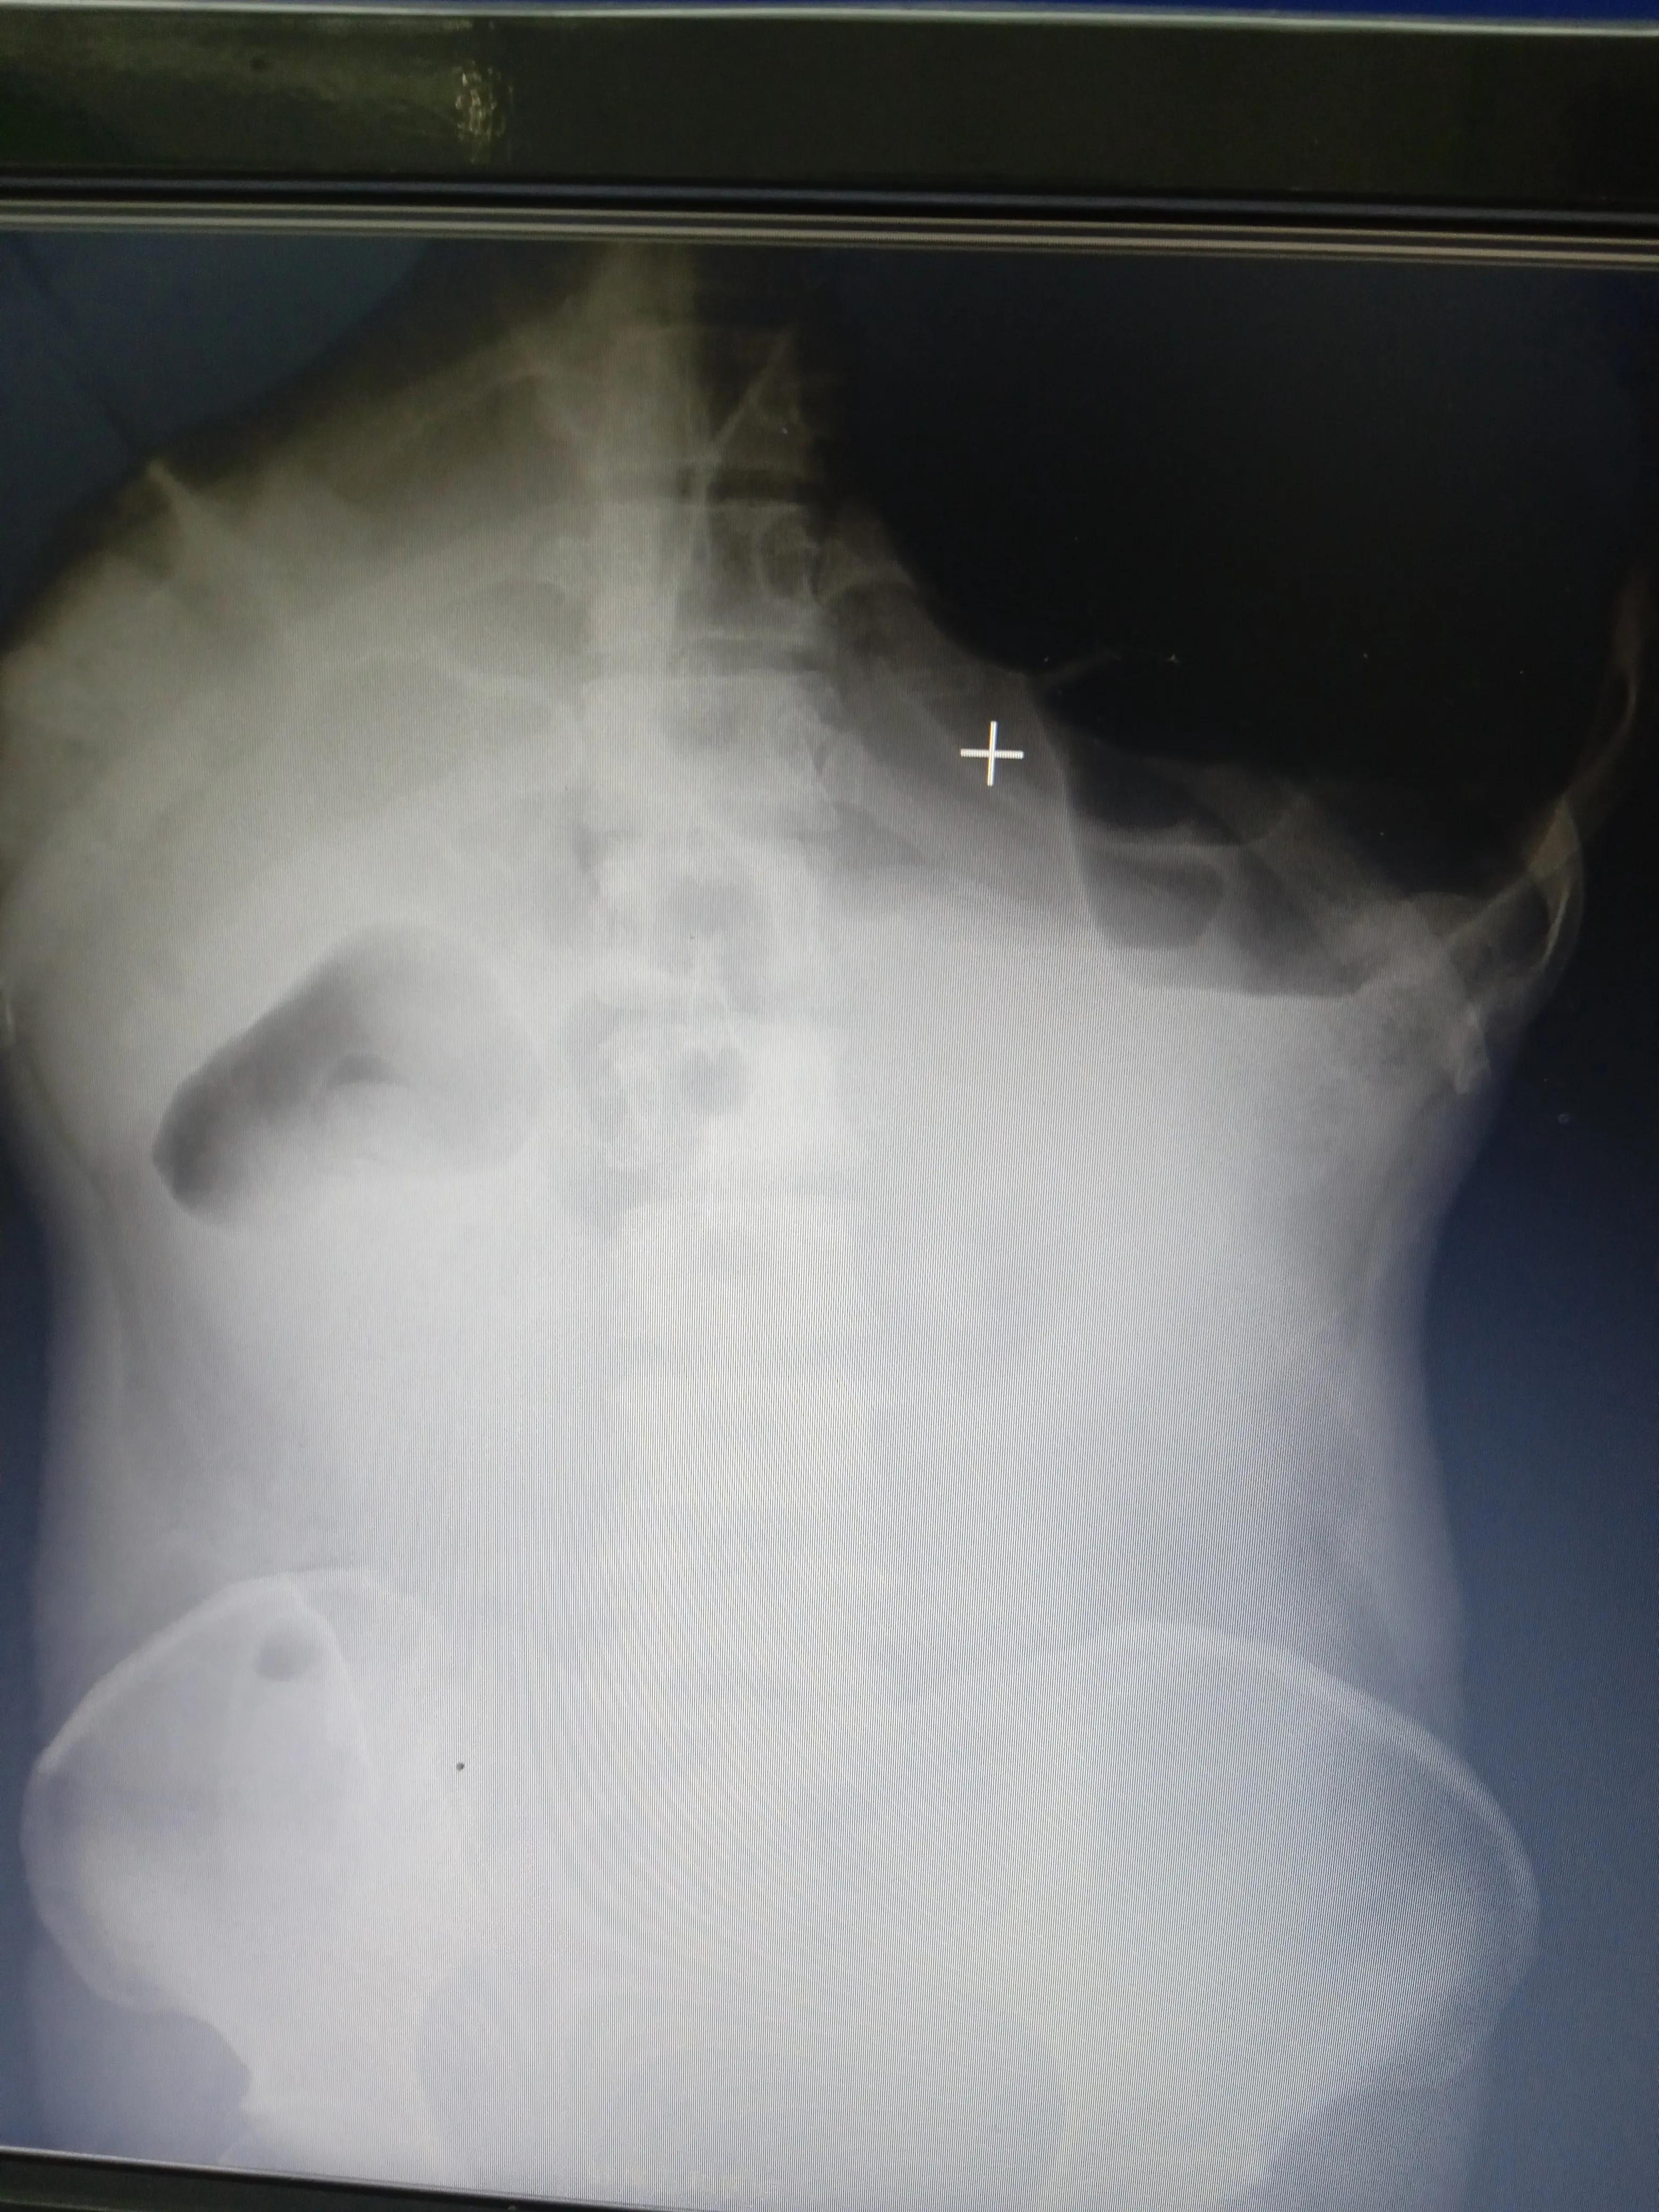

接诊时:腹部膨隆,左上腹压痛及反跳痛明显,肠鸣音亢进,有9次/分钟,闻及气过水声。

询问病史郭大娘“胀”“吐”“痛”“闭”四大典型肠梗阻症状都有了,加上便秘。高度考虑宿便引起肠梗阻。

后来拍腹部立位平片:左中上腹见多发肠管扩张及液平,提示肠梗阻。